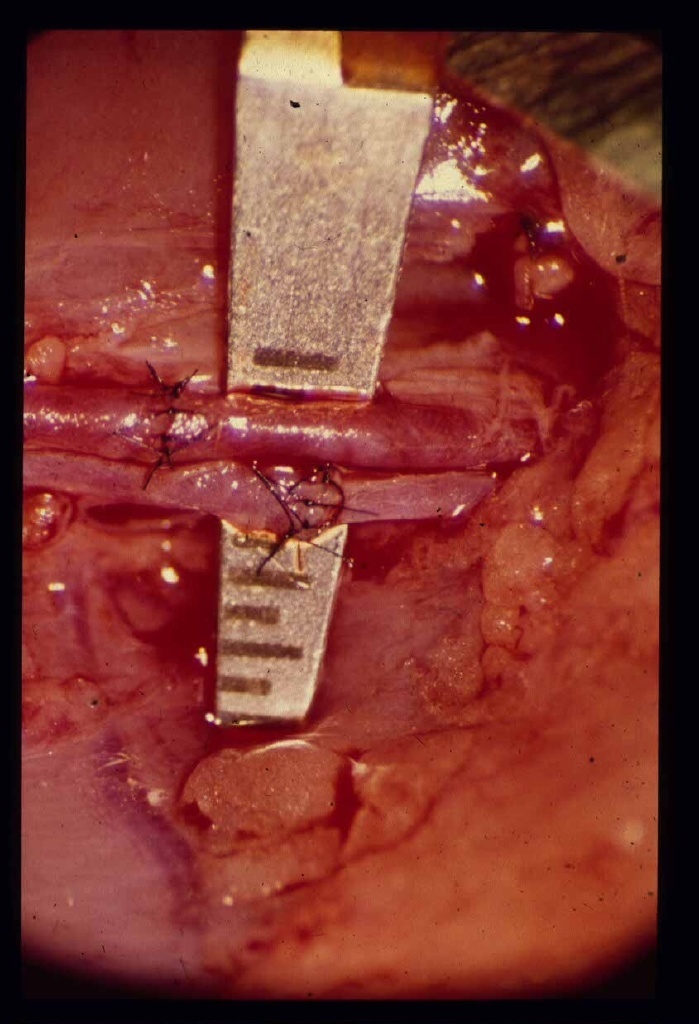

Replantation - darunter verstehen Mediziner das Wiederannähen eines abgetrennten Körperteils. Das Ziel dabei: die Funktion soll ganz oder teilweise wiederhergestellt werden. Ein solcher Eingriff erfolgt über mehrere Schritte: Zunächst fügen Chirurgen die Knochen zusammen, dann die Beugesehnen, Arterien und Nervenhüllen und am Schluss Venen und Strecksehnen. Das ist heute möglich dank der Mikrochirurgie: Mit einem OP-Mikroskop und mittels besonders kleiner Instrumente können Ärzte Blutgefäße wieder verbinden, die lediglich einen Millimeter durchmessen.

In der Klinik für Plastische, Hand- und Wiederherstellungschirurgie im Klinikum Hannover Oststadt wurde vor 25 Jahren erstmals ein Finger wieder angenäht. Seit dieser Zeit sind hier weit mehr als 1.000 solcher Replantationen durchgeführt worden - der größte Teil unter der Leitung von Professor Dr. Alfred Berger. Das Spektrum reicht von Ohren, Nasen über Hände bis zu Füßen. Im Jahr 2001 wechselte die Abteilung von der Medizinischen Hochschule Hannover (MHH) an das Klinikum, der neue Leiter, Professor Dr. Peter M. Vogt, gehört weiterhin zum Lehrkörper der Hochschule. Pro Jahr werden in der Klinik rund 15 Replantationen vorgenommen.